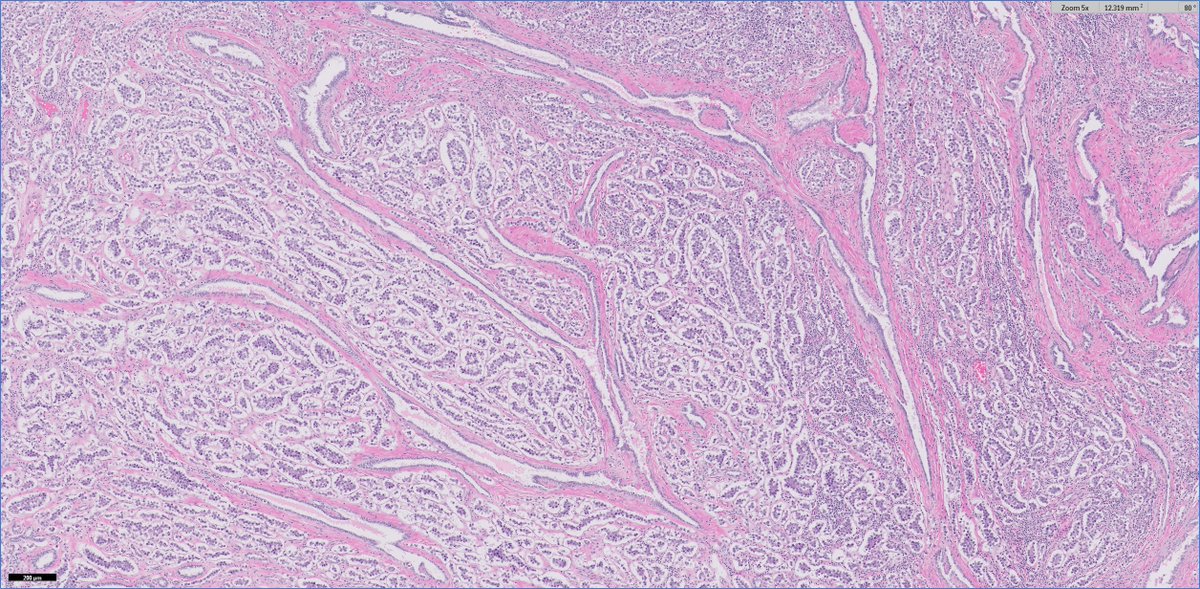

#GUpath🧩 time!

30ish M (no priors) presents with testicular mass and undergoes radical orchiectomy

🔬🤔❓